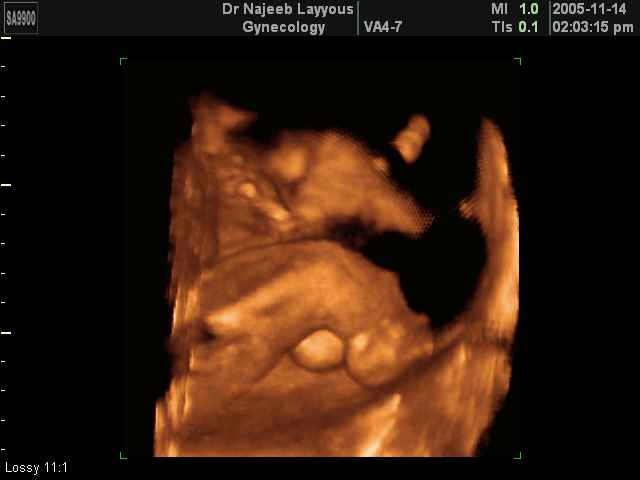

- لقطات فيديو للجنين بجهاز الموجات فوق صوتية رباعي الأبعاد

- صور لأعضاء الجنين